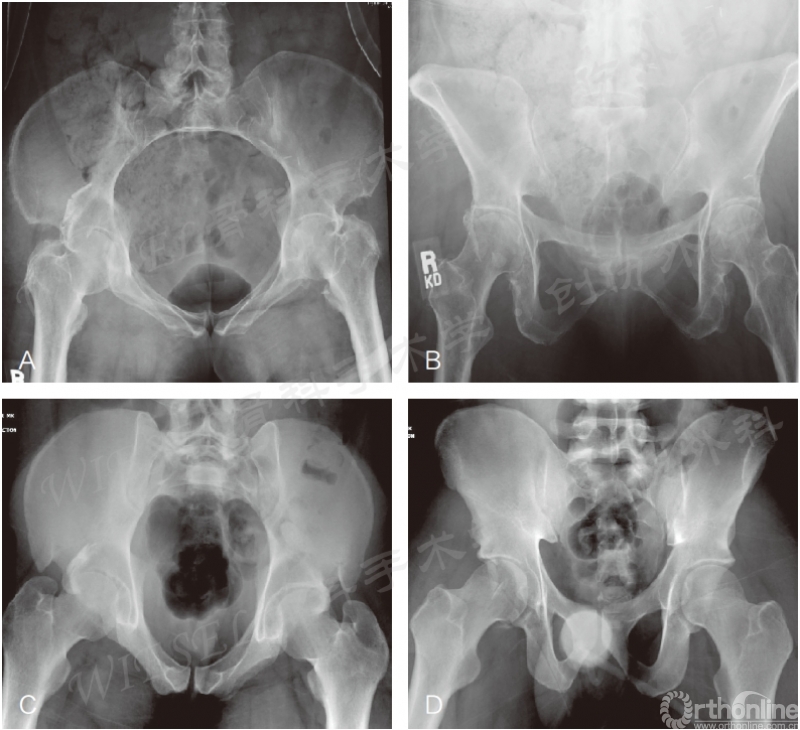

图2 A~D.两性解剖差异举例。女性骨盆形状更圆,耻骨弓成角更钝,因为耻骨体更宽,如一个女性骨盆的入口位(A)和出口位(B)所示。男性的骨盆环更椭圆,因为耻骨体更窄,向前成角更锐,如入口位(C)和出口位(D)所示